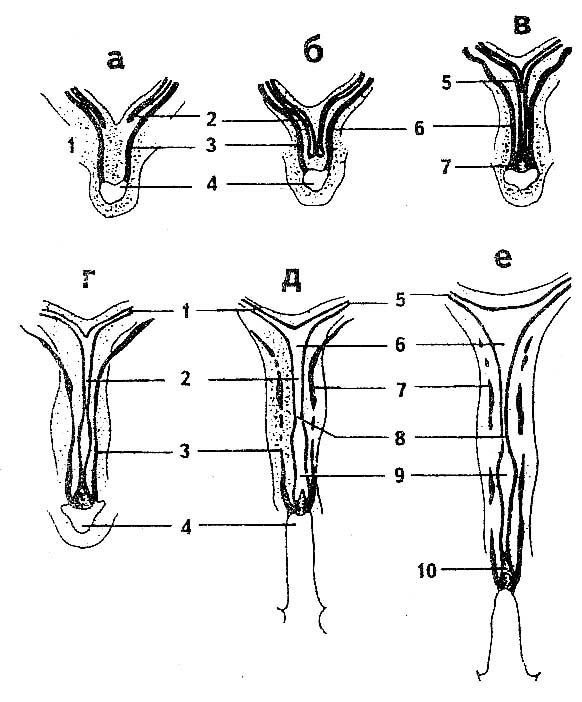

Лабиопластика, также известная как лабиопластика, заключается в хирургической модификации больших или малых половых губ, но чаще всего это уменьшение размера малых половых губ (рис.) и является одной из наиболее часто выполняемых процедур FCGS. Часто цель состоит в том, чтобы сохранить контур губ и сохранить цвет губных краев. Различные хирургические методы включают криволинейную резекцию, резекцию V-образным клином, резекцию нижнего клина и реконструкцию верхнего лоскута на ножке, Z-пластику и другие менее используемые методы.

При изогнутой линейной резекции [9, 10] можно выполнить одну из первых описанных техник, холодную резку, или использовать энергетическое устройство, такое как электрохирургическая игла, лазер или РЧ-генератор. можно использовать для резки.Губная ткань в объеме, необходимом для резекции, подвергается линейной резекции и скульптурированию по желанию, а затем края разреза ремонтируются рассасывающимся тонким швом. Целью этой техники является поддержание минимальной лабиальной длины в 1 см и возможность выступать за пределы интроитуса [11]. Сохранение естественного контура гофрированного свободного края с помощью этой техники невозможно. Однако это зависит от желания пациента, подвергающегося процедуре, и в одном исследовании с 550 женщинами 97% фактически потребовали удаления темных краев [12].К преимуществам относятся небольшие, относительно прямые половые губы, расположенные на одном уровне с большими половыми губами или расположенные ниже них с более розовым краем. Риски включают чрезмерную коррекцию или полную ампутацию, требующую хирургического вмешательства [13].

Резекция V-образным клином, первоначально описанная Alter [14], включает иссечение V-образного клина губной ткани, при этом верхний край V начинается немного ниже препуциальных складок, идущих вниз от капюшона клитора, а нижний край V начинается выше задней комиссуры.Преимущества включают предотвращение чрезмерной резекции и чрезмерного затягивания. Риски включают расслоение краев раны, образование свищей, избыток клиторального капюшона и послеоперационную боль. Резекция V-образным клином была изменена различными способами. Z-пластика [15] — это одна из модификаций, при которой центральный клин половых губ удаляется через разрез в форме буквы «Z». При резекции нижнего клина и реконструкции верхнего лоскута на ножке нижняя часть малых половых губ иссекается, а верхняя часть опускается в виде лоскута на ножке и фиксируется на обнаженном нижнем крае.

Лабиопластика, также известная как лабиопластика, заключается в хирургической модификации больших или малых половых губ, но чаще всего это уменьшение размера малых половых губ (рис.) и является одной из наиболее часто выполняемых процедур FCGS. Часто цель состоит в том, чтобы сохранить контур губ и сохранить цвет губных краев. Различные хирургические методы включают криволинейную резекцию, резекцию V-образным клином, резекцию нижнего клина и реконструкцию верхнего лоскута на ножке, Z-пластику и другие менее используемые методы.

При изогнутой линейной резекции [9, 10] можно выполнить одну из первых описанных техник, холодную резку, или использовать энергетическое устройство, такое как электрохирургическая игла, лазер или РЧ-генератор. можно использовать для резки.Губная ткань в объеме, необходимом для резекции, подвергается линейной резекции и скульптурированию по желанию, а затем края разреза ремонтируются рассасывающимся тонким швом. Целью этой техники является поддержание минимальной лабиальной длины в 1 см и возможность выступать за пределы интроитуса [11]. Сохранение естественного контура гофрированного свободного края с помощью этой техники невозможно. Однако это зависит от желания пациента, подвергающегося процедуре, и в одном исследовании с 550 женщинами 97% фактически потребовали удаления темных краев [12].К преимуществам относятся небольшие, относительно прямые половые губы, расположенные на одном уровне с большими половыми губами или расположенные ниже них с более розовым краем. Риски включают чрезмерную коррекцию или полную ампутацию, требующую хирургического вмешательства [13].

Резекция V-образным клином, первоначально описанная Alter [14], включает иссечение V-образного клина губной ткани, при этом верхний край V начинается немного ниже препуциальных складок, идущих вниз от капюшона клитора, а нижний край V начинается выше задней комиссуры.Преимущества включают предотвращение чрезмерной резекции и чрезмерного затягивания. Риски включают расслоение краев раны, образование свищей, избыток клиторального капюшона и послеоперационную боль. Резекция V-образным клином была изменена различными способами. Z-пластика [15] — это одна из модификаций, при которой центральный клин половых губ удаляется через разрез в форме буквы «Z». При резекции нижнего клина и реконструкции верхнего лоскута на ножке нижняя часть малых половых губ иссекается, а верхняя часть опускается в виде лоскута на ножке и фиксируется на обнаженном нижнем крае.